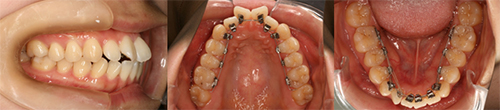

前回の上顎の装置に引き続き、今回は下の歯に矯正装置を装着しました。治療後、自分の初診時の歯型と治療終了時の予測模型(セットアップ模型)とを比べて眺めています。

抜歯せずに前歯のデコボコをならべるために犬歯と奥歯を横に広げるための装置を装着しました。犬歯間を左右に広げ、前歯4本が並べられるだけのスペースを作っていきます。